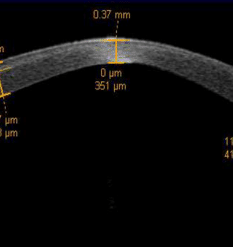

Ectasie cornéenne